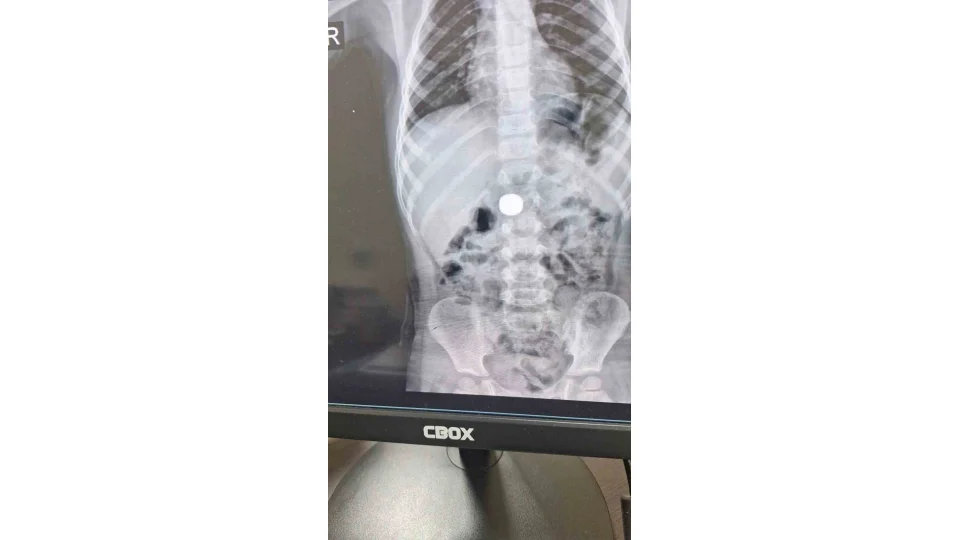

Karaman'da 4 yaşındaki İ.K.'nin mıknatıs yuttuğundan şüphelenen ailesi, Karaman Eğitim ve Araştırma Hastanesi Acil Servisi'ne başvurdu. Yapılan tetkiklerde çocuğun ince bağırsağında iki adet mıknatıs bulunduğu tespit edildi.

Gözlem altına alınan çocuğun sağlık durumu 5 gün boyunca takip edildi. Çocuk Cerrahisi Uzmanı Doç. Dr. Mehmet Uysal'ın gerçekleştirdiği operasyonla bağırsakta tıkanıklığa yol açan iki mıknatıs başarılı bir şekilde çıkarıldı.

Hastayı 5 gün boyunca takibe aldıklarını belirten Doç. Dr. Mehmet Uysal, gözetim süresince çekilen filmlerde mıknatısların yer değiştirmediğini söyledi. Uysal, "Hastayı genel anestezi altında ameliyata aldık. İnce bağırsakta iki mıknatısın birbirine yapışık halde olduğunu gördük. Gerçekleştirdiğimiz operasyonla mıknatısları çıkardık. Ameliyat sonrası hastamız üçüncü gününde taburcu edildi. Şu an genel durumu iyi" dedi.